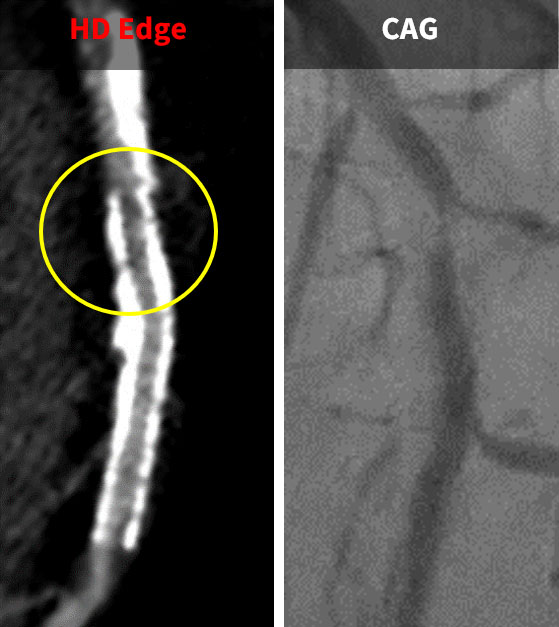

クリニカルへのインパクト:ステント内腔を高分解能に評価

撮影時にHigh-Resolution modeを選択することで、X線焦点を偏向させながら秒間8914viewのサンプリング収集による高分解能画質を得ることが可能です。このモードでは高精細な画像を取得でき、高度石灰化やステントに対してもアーチファクトの少ない画像が得られています。

特にステント評価に対しては、高周波強調関数HD Edgeを使用することで、通常関数のHD Stndに比べてステント内腔の描出能が向上しました。これにより、冠動脈造影(CAG)と比較して、より精度の高い画像を医師に提供できるようになりました(図3、4)。空間分解能の評価としてTTFを計測すると、HD Edgeは高空間周波数帯域で優れた性能を示し、アンダーシュートが発生しない特性を持つことが確認できます(図5)。

患者様の体格によってはノイズが増加することがあるため、ステント留置後の症例に対しては必ずHD EdgeとHD Stndの二つのデータで用いて解析しています。胸部の診断を縦隔条件と肺野条件で行うように、冠動脈も非石灰化プラークや石灰化、ステント内腔評価など目的に応じた画像再構成を実施して診断する必要があると考えています。医師からもHD Edge画像を要望されるケースも増えており、ステント内腔の評価が不十分なためにCAGが実施されるケースは減少しています。

(図4)

HD Edgeでステント内再狭窄を認められ、

CAGにおいて同部位に狭窄が確認された。